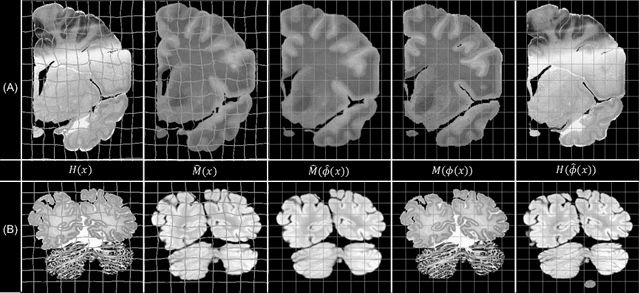

Abstract:Joint registration of a stack of 2D histological sections to recover 3D structure (3D histology reconstruction) finds application in areas such as atlas building and validation of in vivo imaging. Straighforward pairwise registration of neighbouring sections yields smooth reconstructions but has well-known problems such as banana effect (straightening of curved structures) and z-shift (drift). While these problems can be alleviated with an external, linearly aligned reference (e.g., Magnetic Resonance images), registration is often inaccurate due to contrast differences and the strong nonlinear distortion of the tissue, including artefacts such as folds and tears. In this paper, we present a probabilistic model of spatial deformation that yields reconstructions for multiple histological stains that that are jointly smooth, robust to outliers, and follow the reference shape. The model relies on a spanning tree of latent transforms connecting all the sections and slices, and assumes that the registration between any pair of images can be see as a noisy version of the composition of (possibly inverted) latent transforms connecting the two images. Bayesian inference is used to compute the most likely latent transforms given a set of pairwise registrations between image pairs within and across modalities. Results on synthetic deformations on multiple MR modalities, show that our method can accurately and robustly register multiple contrasts even in the presence of outliers. The 3D histology reconstruction of two stains (Nissl and parvalbumin) from the Allen human brain atlas, show its benefits on real data with severe distortions. We also provide the correspondence to MNI space, bridging the gap between two of the most used atlases in histology and MRI. Data is available at https://openneuro.org/datasets/ds003590 and code at https://github.com/acasamitjana/3dhirest.